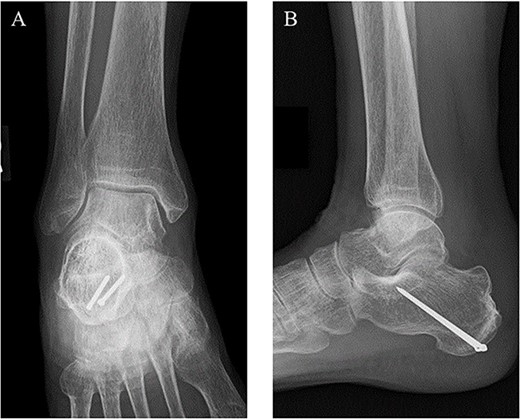

Postoperatively, a non-weightbearing short leg cast was applied for 2 weeks, and when the cast was removed, active and passive ranges of motion exercises of the ankle were started. Partial-weightbearing was allowed at 2 weeks postoperatively, and full-weightbearing at 6 weeks postoperatively. At 3 months after the surgery, non-contrast CT showed complete bone union (Fig. 4). At 2 years after the surgery, she had no symptoms and dysfunctions (Fig. 5).

At 2 years after the surgery, plain radiographs of the right ankle showed complete bone union without the deformity of the fracture site and the backing out of the implants in (A) anteroposterior and (B) lateral views.